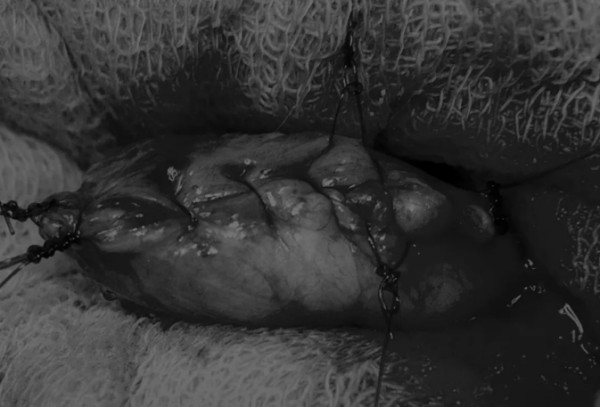

图4 这张图显示了从膀胱中取出的大量结石